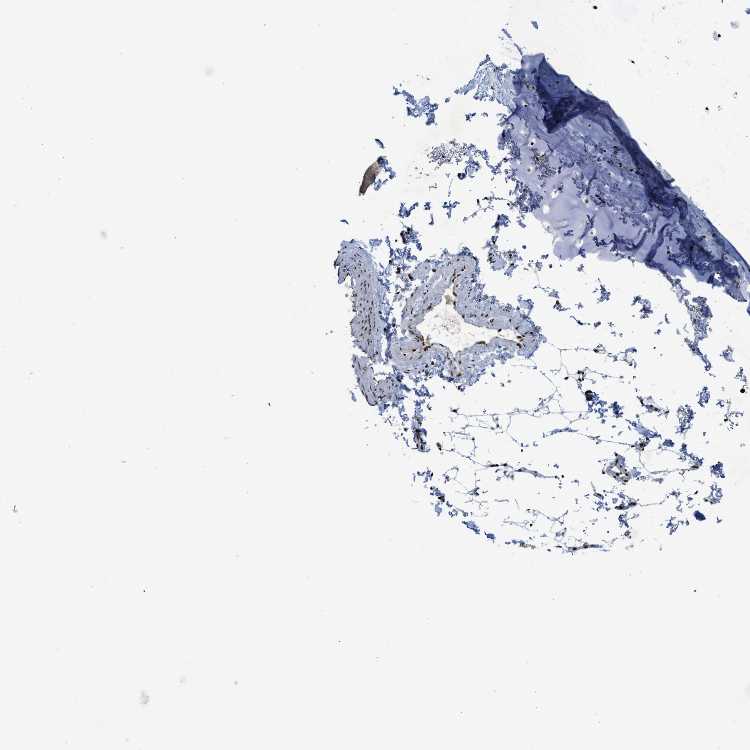

SOFT TISSUE 1 - Antibody stainingi

Antibody staining in the annotated cell types in the current human tissue is reported as not detected, low, medium, or high, based on conventional immunohistochemistry profiling in selected tissues. This score is based on the combination of the staining intensity and fraction of stained cells.

Each image is clickable and will lead to virtual microscopy that enables deeper exploration of all samples and also displays staining intensity scores, fraction scores and subcellular localization as well as patient and tissue information for each sample.

Antibody HPA018319Antibody HPA018668Antibody HPA021504Antibody HPA028807

Chondrocytes High---

Fibroblasts HighLow-Not detected

Peripheral nerve HighNot detectedLowLow